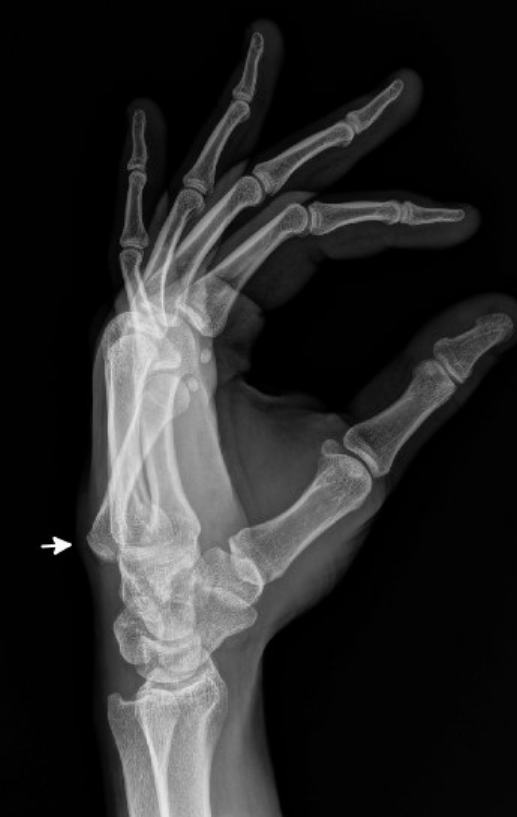

The patient punched a wall in an episode of frustration with his left hand and has pain and swelling over the ulnar aspect of his hand and wrist. What is the diagnosis?